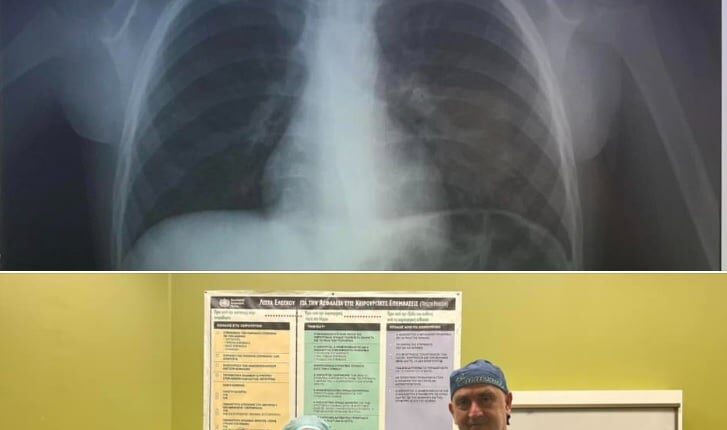

Μία περιπέτεια έζησε ένα 4χρονο παιδί την παραμονή της Πρωτοχρονιάς στο Ηράκλειο, καθώς μεταφέρθηκε στο εσπευσμένα στο νοσοκομείο αφού κατάπιε κέρμα και δεν μπορούσε να αναπνεύσει.

Άμεσα οδηγήθηκε στο ΠΑΓΝΗ με τους γιατρούς να προχωρούν σε επείγουσα αφαίρεση η οποία στέφθηκε με επιτυχία, σύμφωνα με το cretapost.gr.

Το περιστατικό γνωστοποιήθηκε από την ΩΡΛ κλινική του νοσοκομείου μέσω ανάρτησης στα κοινωνικά δίκτυα: